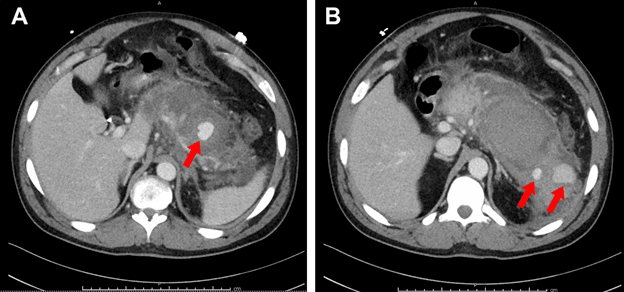

The patient was admitted to our hospital's surgical intensive care unit hemodynamically stable with initial hemoglobin of 10.8 g/dL. He was urgently brought to the interventional radiology (IR) suite, where conventional angiography identified three pseudoaneurysms of the splenic artery. Successful coil angioembolization of all three visceral artery pseudoaneurysms (VA-PSA) was achieved. Repeat CECT two days later identified three additional VA-PSA arising from the superior pancreaticoduodenal arcade (PDA). All three VA-PSA were successfully angioembolized with a second angiographic procedure (Figure 2).

Figure 2. Angiography demonstrating three VA-PSAs of splenic artery (L) and three VA-PSAs of pancreaticoduodenal arcade (R)